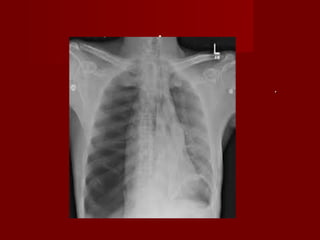

 RX TORAX :ENSANCHAMIENTO MEDIASTINALRX TORAX :ENSANCHAMIENTO MEDIASTINAL

 DESVIACION TRAQUEA A DERECHA PERDIDA DELDESVIACION TRAQUEA A DERECHA PERDIDA DEL

CONTORNO BOTON AORTICO.CONTORNO BOTON AORTICO.